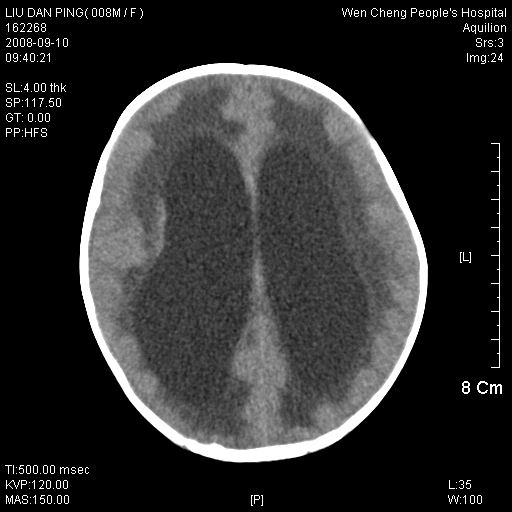

以下是引用卜一在2008-9-10 16:21:00的发言:[br]髓母细胞瘤伴梗阻性脑积水!支持![br]髓母细胞瘤特点:—般直径大于3.5cm,位于后颅凹中线之小脑蚓部。累及上蚓部的肿瘤延伸到小脑幕切迹之上,ct平扫肿瘤多呈均匀一致的高或等密度病灶,增强检查呈均匀一致的强化。病灶中有小坏死时,平扫亦可呈不均匀之混杂密度,注药后有增强。[br]

以下是引用zjzjr在2008-9-10 15:09:00的发言:[br]髓母细胞瘤伴梗阻性脑积水.